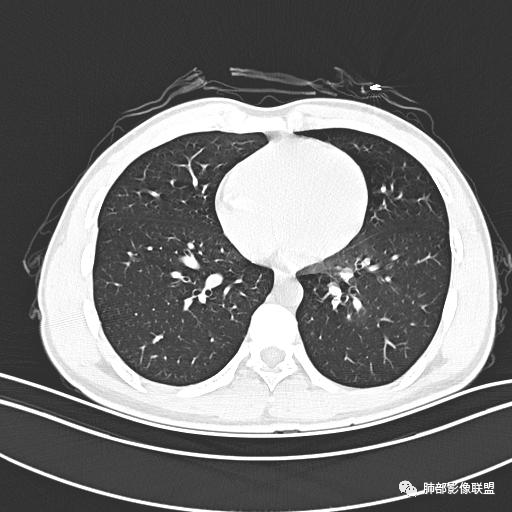

男,19岁

主  诉:发热、全身皮疹2天。

现病史:患者源于2天前受凉后出现发热,最高体温为38.5℃,且颜面部出现少量皮疹,无鼻塞、流涕、咳嗽、咳痰,未在意而未作特殊处理,次日全身皮疹逐渐增多至全身,伴轻度瘙痒,在当地卫生所给予抗病毒、抗感染治疗(具体用药不详)体温有所下降,但皮疹无明显消退,无腹痛、头痛,食欲无明显减退,为进一步诊治,遂于今日急来我院求治,患者目前精神尚可,体力正常,食欲正常,睡眠正常,体重无明显变化,大便正常,排尿正常。

小强:青年,发热,皮疹;双肺散在结节,周围磨玻璃,点晕征,疱疹病毒感染,鉴别荚膜组织胞浆菌,结核。 大雄:青年,急性起病,发热伴全身皮疹2天,抗病毒治疗体温有下降。双肺随机分布大小不等类圆结节,“点晕征”。考虑水痘-疱疹病毒(VZV)血播询问接触史,查体皮疹分布以及形态基本可诊断。 王开金江津中心医院呼吸科:青年男性,起病急,病程短,以发热,皮疹为首发症状,感染指标以单核细胞升高为主,胸部ct双肺多发结界,周围有晕,点晕表现,随机分布,同意於老师意见,水痘疱疹病毒血流感染累及肺。 王秀仙:双肺多发大小不等结节,周围有晕,边缘模糊,呈点晕征表现。青年,急性起病,发热伴全身皮疹2天,抗病毒治疗体温有下降。考虑疱疹病毒。鉴别荚膜组织胞浆菌。 傅昌瑜:19岁男性,发热、全身皮疹2天,单核细胞增高,双肺多发结节,结节边缘见边界不清磨玻璃影。点晕征+发热、全身皮疹+单核细胞增高——考虑水痘-带状疱疹病毒肺炎。 一切∮随缘:年轻男性,发热,皮疹两天,实验室,CRP,PCT增高,影像:双肺多发散在磨玻璃结节,边界欠清,大小不等,呈点晕征改变,以血管束周围分布为主,局部血管束略增粗,其它无明显改变,考虑:1:病毒性肺炎(水痘疱疹病毒?不知道皮肤有无改变)2:真菌(组织胞浆菌,血管侵袭性肺曲霉)3:GPA4:寄生虫(实验室没有看到嗜酸细胞增高) 赵山河:双肺散在结节,周围有晕,边缘模糊,呈点晕征表现。青年,急性起病,发热伴全身皮疹2天,抗病毒治疗体温有下降。考虑水痘—疱疹病毒感染。洪桥爱:青年男性,发热、皮疹2天,伴瘙痒,皮疹于面部首发,之后进展至全身,虽然没有对皮疹进行描述,但是从出疹时间及皮疹进展情况,伴瘙痒,应该就是个水痘患者;CT提示双肺随机分布结节影,部分结节伴有边界不清晕征,考虑水痘血播肺。 刘强:年轻男性,急性起病,皮疹,发热,抗感染治疗体温下降,说明有效。影像表现为散在点晕征,感染类疾病谱(疱疹病毒,真菌,结核),结合年龄,皮肤皮疹,考虑水痘-疱疹病毒性肺炎。 小兜:男性,19岁,发热皮疹两天,颜面部至全身,CRP,降钙素及单核增高。CT示双肺散在小结节,周围伴磨玻璃影,点晕征,考虑为水痘-带状疱疹病毒(varicella-zoster virus,VZV)肺炎 必有路:青年,皮疹+发热+“点晕征”→水痘-疱疹病毒(VZV) 许慧良:青年男性患者,发热、皮疹2天,体温最高38.5℃,第3天皮疹扩展至全身,伴瘙痒,胸部CT:双肺多发随机分布的小结节,结节周边见边界模糊的晕征,考虑水痘病毒感染流心明智:男,19,急性起病,发热伴全身皮疹2天。出疹顺序头→全身,抗病毒有效。胸部CT:两肺多发大小不等类圆形实性小结节影,随机分布,结节周围环绕GGO,边界模糊,呈点晕征。出疹特点是关键,未提示。考虑:血播病毒性肺炎,水痘-疱疹病毒?麻疹?鉴别荚膜组织胞浆菌、TB、血管炎、寄生虫等。 浪迹天涯:病灶多为5-10mm大小结节,结节周围可见磨玻璃样的晕环,常多发,可分布于肺内任何区域,考虑水痘—带状疱疹病肺炎如果短时间内有新的一个区域浸润,更加能说明,